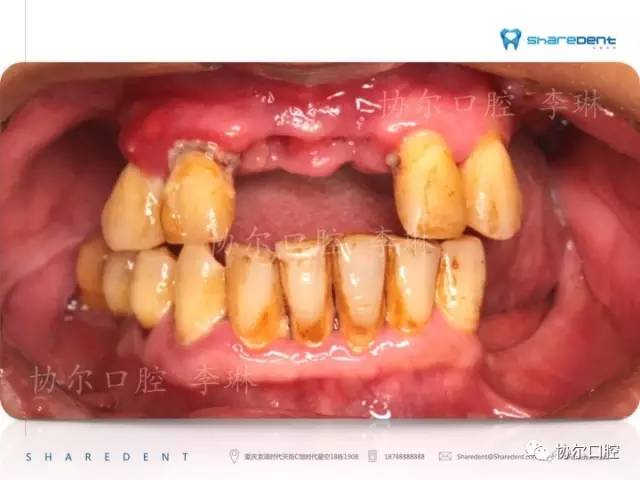

如图所示,慢性牙周炎的发生是一进展过程,最开始可能只有牙龈红肿等症状,有些朋友甚至并无任何不适,只是检查时才发现牙龈出血、牙石等情况存在。或许部分朋友会将其归咎于上火,吃下火的药,甚至服用抗生素,然而治标不治本。

病灶—牙结石、菌斑等依旧在老地方日积月累地攻击牙周组织(不仅仅是牙龈软组织,也包括牙龈覆盖处的骨组织),不及时清除最终导致了牙周炎。

我常常跟朋友们说,牙齿所在的地方和胳膊腿一样,表面是肉(牙龈),肉盖住的是骨头(牙槽骨)。牙齿长在骨头里,如树深植土壤中。当水土流失后,树就渐渐失去营养和支撑、最终倒下,同样地,病灶导致牙槽骨吸收,牙齿的支持力量减少,进而发生松动甚至脱落。